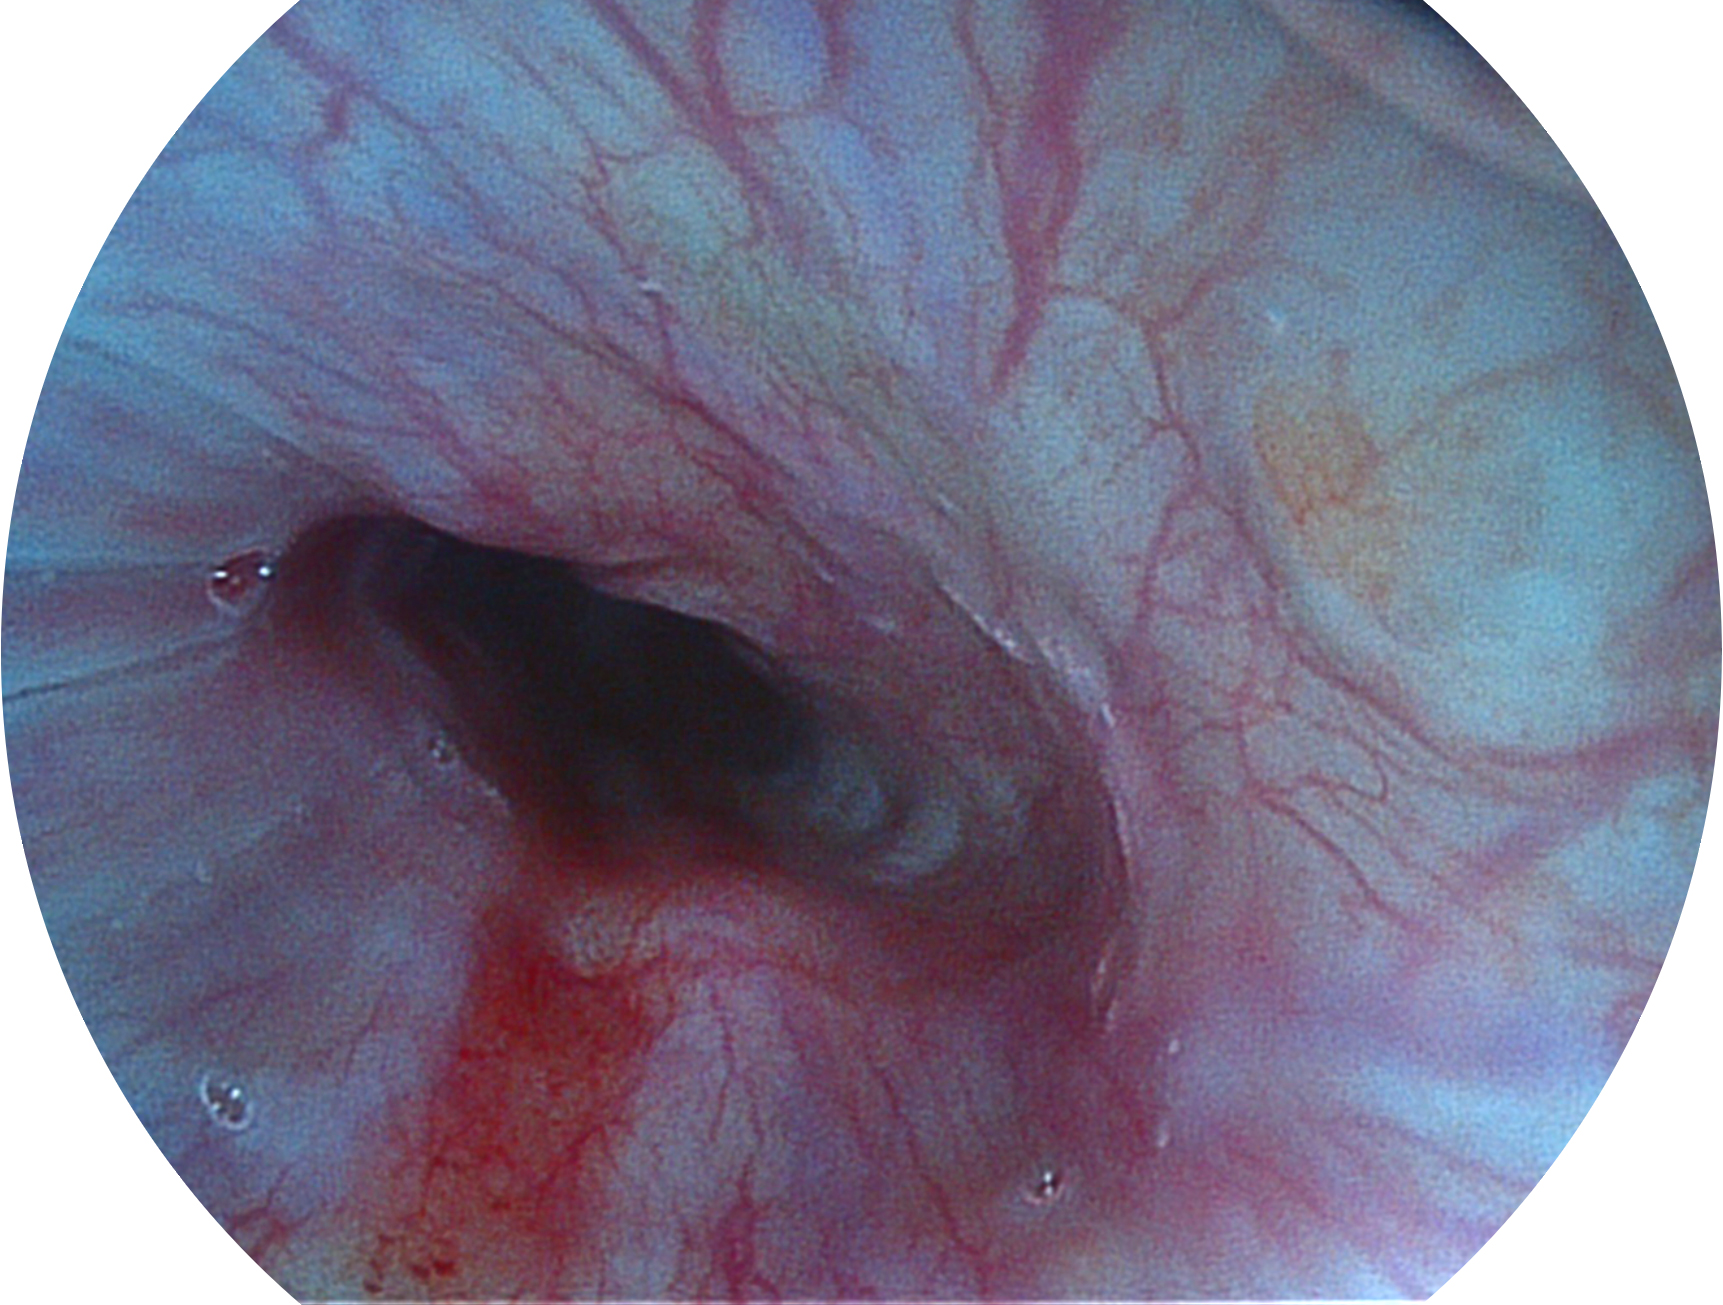

百老汇电子游戏官网新开发的内镜染色技术,主要是基于多波长LED 光源的开发,VLS-55Q 四波长LED 光源是由四个不同颜色的LED光按照相应照明模式所规定的特定发光比例进行合束后形成,合束后形成的照明光的光谱由红光、绿光、蓝光及蓝紫光这四个不同的波段范围构成。具有更高光谱自由度,通过光谱比例的控制,实现了聚谱成像技术,英文全称为“Spectral Focused Imaging, SFI”,缩写为“SFI”和光电复合染色成像技术,英文全称为“Versatile Intelligent Staining Technology, VIST”,缩写为“VIST”。